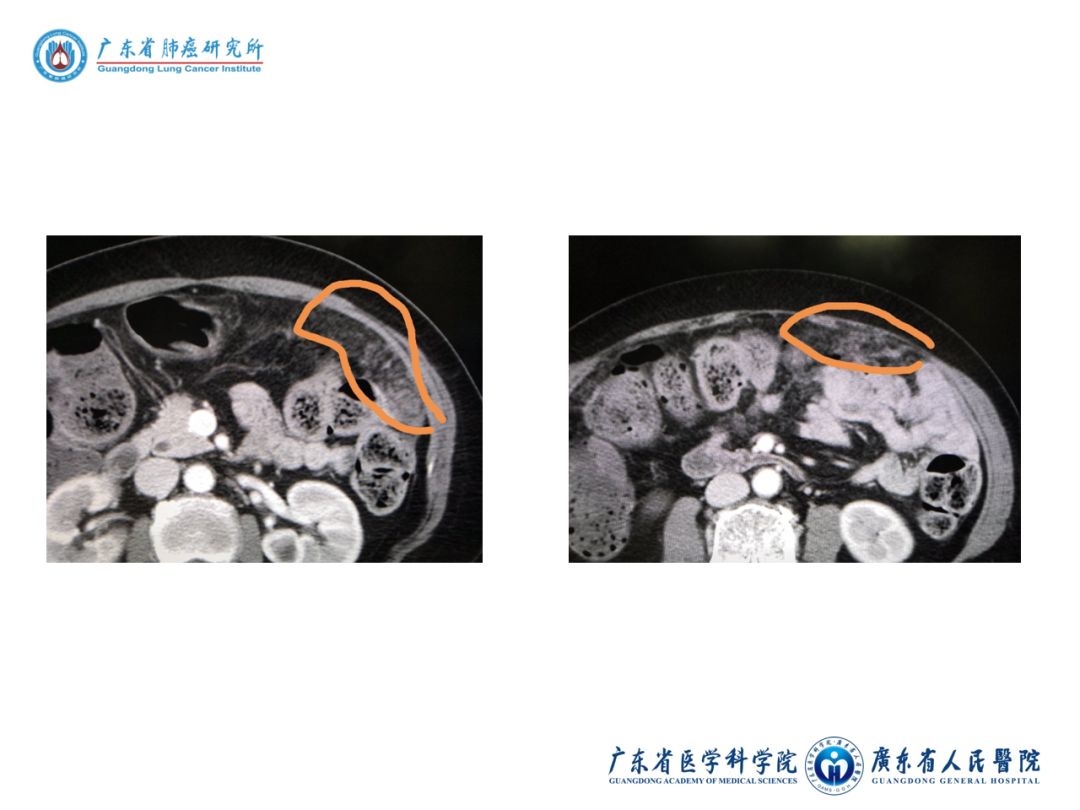

10)2019-3-18胸+全腹增强CT:

① 右肺中叶肺癌,与2019-1-31CT相比,无明显变化。

② 右侧胸膜增厚,右侧胸腔少量积液,大致同前。T4、T6、T8椎体改变,考虑转移瘤,同前相仿。上中腹部肠系膜、腹膜改变,考虑多发转移可能性大。盆腔少量积液。

病例小结

4)二线:AZD3759治疗6周,混合疗效:脑膜强化灶基本消失,上中腹部肠系膜、腹膜改变,考虑多发转移可能性大。盆腔少量积液。肺部稳定。目前1度头晕头痛、1度恶心、2度呕吐。